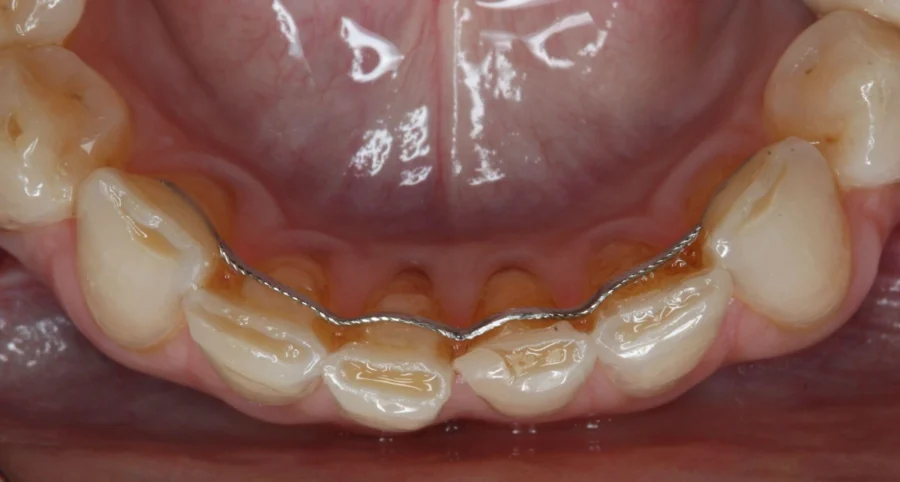

Y si tengo bruxismo, ¿Necesito una férula de descarga?

Sí. La férula de descarga se confecciona de una manera u otra en función del tipo de bruxismo.

Hay dos tipos de bruxismo: el céntrico y el excéntrico. El bruxismo céntrico se entiende como ‘’apretamiento dental’’ de los dientes superiores contra los inferiores. El bruxismo excéntrico se entiende como ‘’rechinamiento dental’’ de los dientes superiores contra los inferiores.

En función de los signos y síntomas presentes. El bruxismo céntrico suele manifestarse con dolor en los músculos implicados en la masticación, y a nivel dental, con facetas de desgaste leves, a veces inexistentes, en las caras oclusales de los molares.